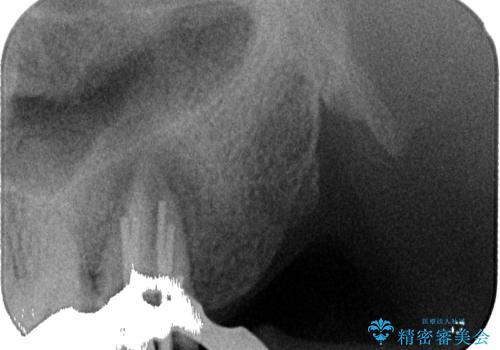

骨の透過像が非常に大きく、根管も大きく削られていたため、歯根破折による抜歯の可能性がありましたが、根管治療可能な状態でした。

初回治療後には速やかに痛みが改善され、非常に大きかったレントゲンでの骨透過像も改善されました。